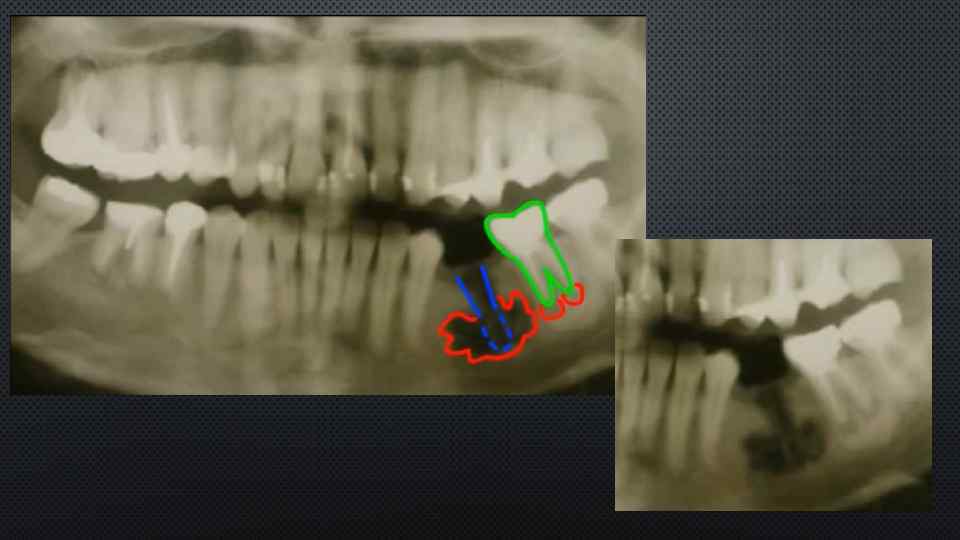

Клинический случай Острый одонтогенный остеомиелит нижней челюсти слева • Клинический диагноз: Острый одонтогенный остеомиелит нижней челюсти слева. Подчелюстной лимфаденит слева. Повышенный рвотный рефлекс

Предварительный диагноз • • Предварительный диагноз: острый одонтогенный остеомиелит нижней челюсти слева. • Открывание рта не ограничено. В полости рта 37 разрушен на 23, слизистая оболочка вокруг отечная, пальпация болезненная. Перкуссия 37 болезненная. Переходная складка в области 35, 36, 37 сглажена. Слизистая оболочка альвеолярного отростка гиперемирована и отечна как со стороны преддверия полости рта, так и с небной стороны, высыпаний нет. Десны отечны и гиперемированы, не кровоточивы, разрыхлены. Язык нормальной формы и величины, влажный, обложен, выраженность сосочков в пределах нормы. Трещин, прикусов, язвочек нет. Слизистая глотки розового цвета, влажная, гладкая, блестящая, налетов, изъязвлений, рубцов нет. • Обоснование: диагноз поставлен на основании жалоб больного на острые, постоянные, интенсивные боли локализующиеся в нижней челюсти слева; данных анамнеза заболевания о том, что считает себя больным около двух дней, когда заболел зуб на нижней челюсти слева, появился отек, повышение температуры тела до 38 С. ; данных обьективного исследования - незначительная ассиметрия лица за счет воспалительного отека мягких тканей нижней челюсти слева. При пальпации определяется болезненность по наружной поверхности челюсти в области воспалительного очага

• данных рентгенографии нижней челюсти: на рентгенографии нижней челюсти слева - очаг деструкции костной ткани в области корней 37 с четким контуром, диаметр 1, 0 см